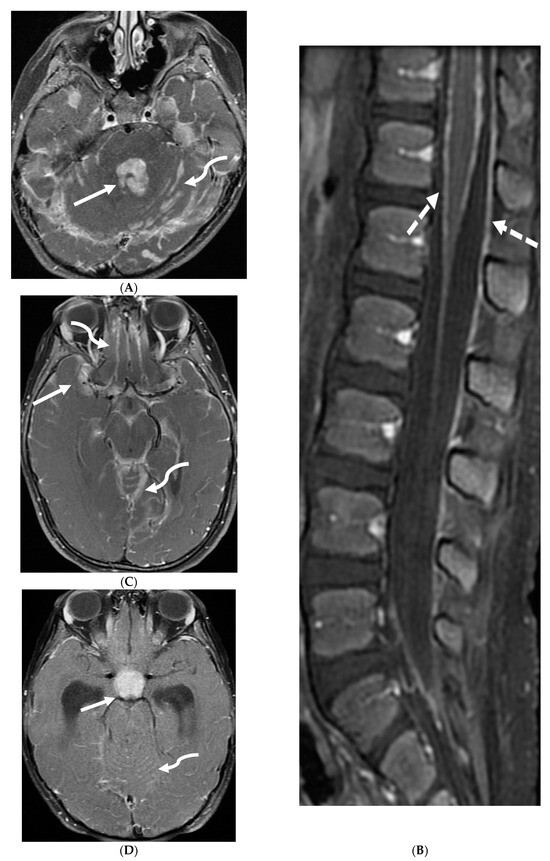

Prototheca species are unicellular algae that are typically known to involve the cutaneous and subcutaneous tissues in humans [6]. Systemic involvement, although rare, can cause meningitis, peritonitis, endocarditis, etc. and is commonly seen in immunodeficient individuals [7]. Prototheca spp. infections are usually exogenous and associated with traumatic inoculation from contaminated soil or water. They can also occur from surgery or catheterization, and even insect bites [8]. Exposure leads to chronic granulomatous inflammation with necrosis [6]. Notably, diagnosis of protothecosis may be challenging as it is not easily identified on Hematoxylin and eosin (H&E) or routine fungal stains, and mimics many fungal infections such as Coccidiodes, Blastomyces. Imaging findings include diffuse LME along the cortical sulci and spinal cord, with multiple loculations given the chronic inflammatory response. These loculations characteristically cause mass effect leading to a flattened and deformed spinal cord (Figure 2) [9].

Figure 2.

Post contrast sagittal T1 brain (A), T1 spine (B), axial T1 brain (C) and spine (D): 17-year-old girl with couple of years of fatigue, shuffling gait, back/lower extremity pain. There is moderate ventriculomegaly (white star). Meningeal enhancement is present around the cervical cord (white arrow). Flattened and deformed brainstem & spinal cord diffusely (curved arrows) and enhancing septae (dashed arrows) within the thecal sac are noted likely from chronic meningitis. Basal cistern enhancement (open arrow) and septae (arrow head) in the lateral ventricles likely reflects sequela of chronic inflammation/infection. Pathology: Prototheca Zopfil.